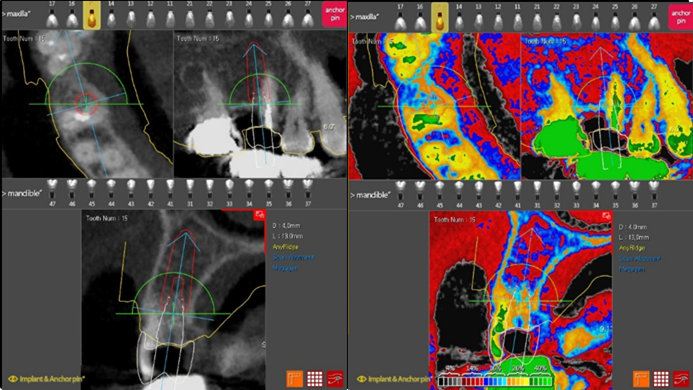

Dr. Kwang Bum Park, digital guided surgery, bone regeneration, maxillary posterior, #13, #14, guided surgery, GBR, AnyRidge, i-GEN, Mega-Oss, R2GATE, R2GATE Full surgical kit

Products:

AnyRidge implant system, R2GATE Guide, R2GATE surgical kit (AnyRidge), Mega ISQ, Mega-Oss